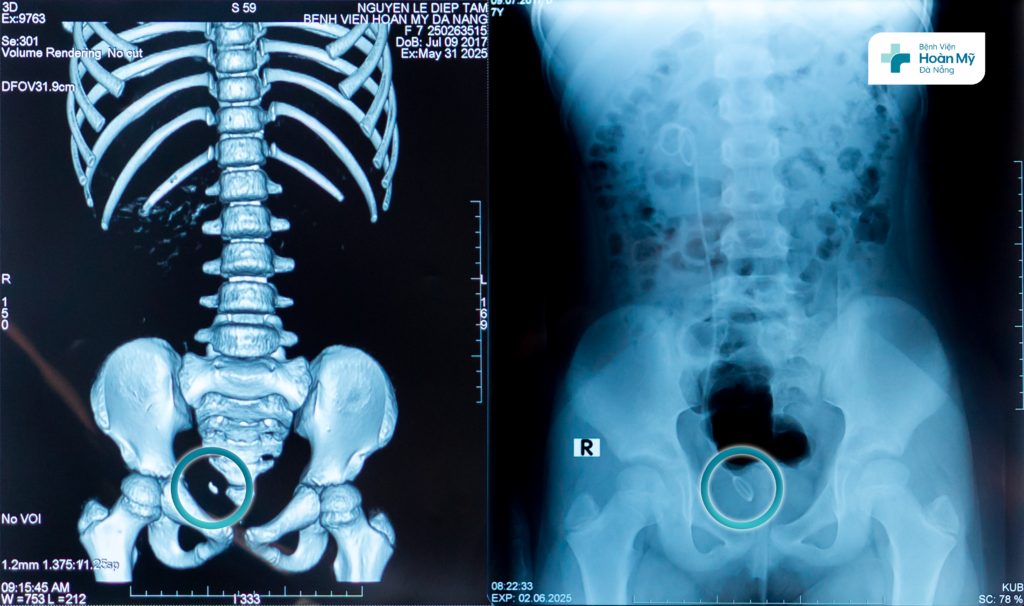

Bé N.T.Tâm (8 tuổi, trú tỉnh Quảng Nam), đau quặn hông phải nhiều được mẹ đưa đi khám và được chẩn đoán sỏi niệu quản phải 1/3 dưới, điều trị nội khoa nhiều đợt ở các bệnh viện khác nhau nhưng không hiệu quả.

Đầu tháng 6/2025, gia đình đưa trẻ đến Bệnh viện Hoàn Mỹ Đà Nẵng khám và tìm kiếm phương pháp điều trị cho con. Sau thăm khám, siêu âm, chụp CT liều thấp chẩn đoán, các bác sĩ quyết định lựa chọn phương pháp tán sỏi ngược dòng nhằm loại bỏ viên sỏi, đồng thời đảm bảo an toàn, thẩm mỹ cho trẻ.

Bệnh nhi sạch sỏi niệu quản sau điều trị nội soi tán sỏi ngược dòng

2 ngày sau phẫu thuật, trẻ đã ổn định, hết đau, dòng tiểu thông thoáng, kiểm tra trên phim thấy sạch sỏi và có thể xuất viện về nhà.